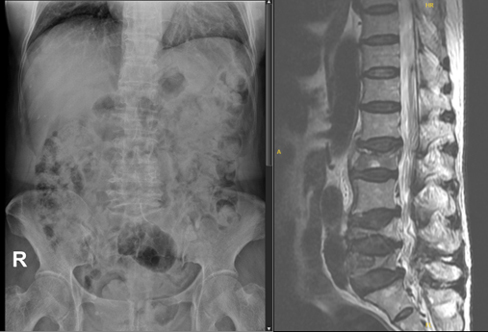

Case 9: 76-year-old female with lumbar compression fracture and bone marrow oedema

Romosozumab → Denosumab